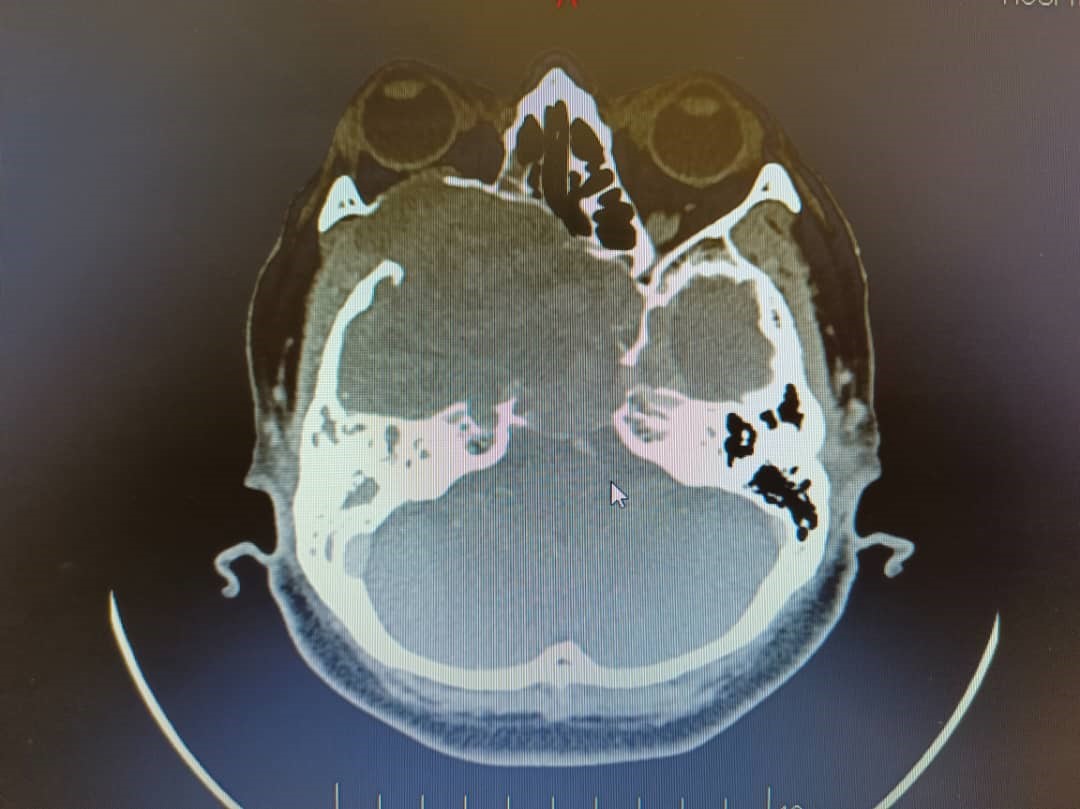

Schwannomas, also known as neurilemmomas, are benign nerve sheath tumors originating from Schwann cells of the peripheral nervous system. Sinonasal schwannomas are rare, comprising approximately 4% of all schwannomas. These tumors are typically slow growing, often leading to delayed clinical presentation. Despite their benign nature, their indolent progression can result in significant morbidity due to mass effect on adjacent vital structures. We report a case of a large, late-diagnosed right sinonasal ancient schwannoma causing extensive compression of surrounding tissues, including the right frontal and temporal lobes, ultimately resulting in vision loss due to compressive optic neuropathy. Ocular symptoms may be the initial manifestation of sinonasal tumors and should raise concern for potentially aggressive lesions. Prompt recognition and early referral are critical to minimize complications and improve patient outcomes.